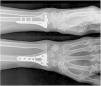

Intervención: Luego de 10 días del trauma se le practicó reducción abierta más osteosíntesis con placa de bloqueo volar (fig. 7). En control de ortopedia a los 21 días del posquirúrgico presenta limitación funcional total de mano y muñeca derecha, ocasionada por el dolor y el edema. Después de 27 días del posquirúrgico inició el proceso de rehabilitación, asistió a 10 sesiones de terapia física y a 10 sesiones de terapia de movilización pasiva con órtesis robótica (fig. 8).

Resultados: inicialmente se encontró una puntuación en la escala DASH de 75.83 y en la escala EVA de 8; después de 4 semanas de rehabilitación complementada por órtesis robótica, mejoró la funcionalidad según DASH a 2.50 y disminuyó el dolor según EVA a 0. Además, mejoró los arcos de movilidad articular de la muñeca en extensión de 15 a 30 grados, en flexión de 30 a 50 grados, la desviación radial de 10 a 15 grados, y la desviación ulnar de 10 a 15 grados. La paciente inició las actividades de la vida diaria luego de la tercera semana de rehabilitación, y no se reportaron eventos adversos durante la intervención. (Tabla VII y VIII)